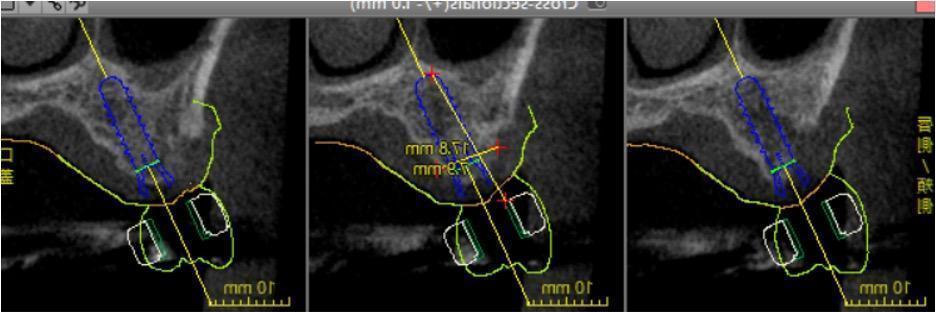

今では技術が進み、CT画像と歯並びの光学スキャン画像を重ね合わせて、パソコンで3次元でお口の状態が確認できるので、そこで知識を駆使してインプラントを配置し、「リスクの少ない方法」と「長期予後」を考えて手術計画を決定いたします。

インプラントの埋入深さ、ハウスフィールドユニット、インプラントの形状、手術ガイドの使用の有無、隣在歯との距離、神経との距離等、さまざまな事を考えます。